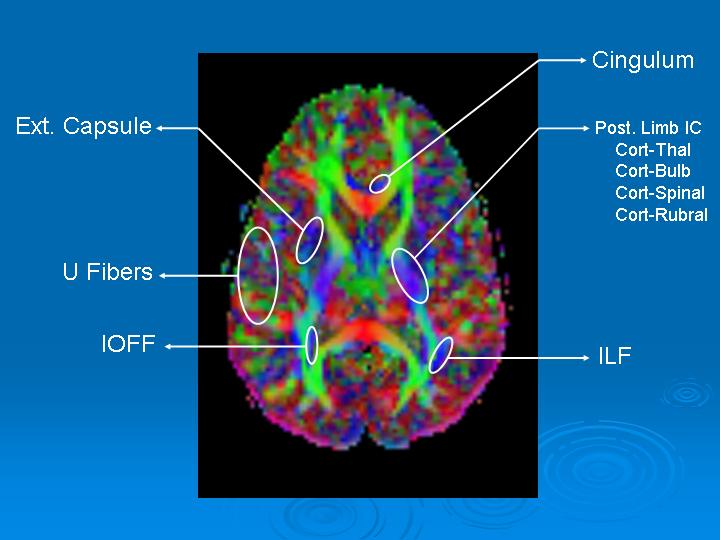

Cerebral tracts may be presented in 2D color images in: axial, coronal, and sagittal planes. The relational topographic appearance of the tracts are better identified in planes that are perpendicular to the major axis of the tract. For example, the corpus callosum which is an axial structure is better defined in the sagittal or coronal view. Thus, tracts going anterior-posterior or posterior-anterior are better seen in coronal view. Descending and ascending tracts are better depicted in axial view (Figure 1).

Figure 1. Axial FA Map. We have targeted blue fibers which encodes for foot-head or head-foot direction.

- Ext: External.

- IC: Internal Capsule

- IOFF: Inferior Occipito-Frontal Fasciculus

- Post: Posterior

- Cort: Cortical

- Thal: Thalamic

- Bulb: Bulbar

- ILF: Inferior Longitudinal Fasciculus

Notice that the portion of the ILF and IOFF shown are just some bundles ascending in the posterior portions as these fasciculi are predominantly posterio-anterior oriented.